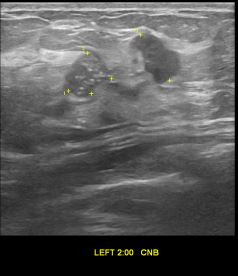

상기환자는 외부검사 이상소견으로 내원하신 50대중반 여성분으로 의심스러운 좌측혹

조직검사 시행해 유방암으로 진단되었습니다